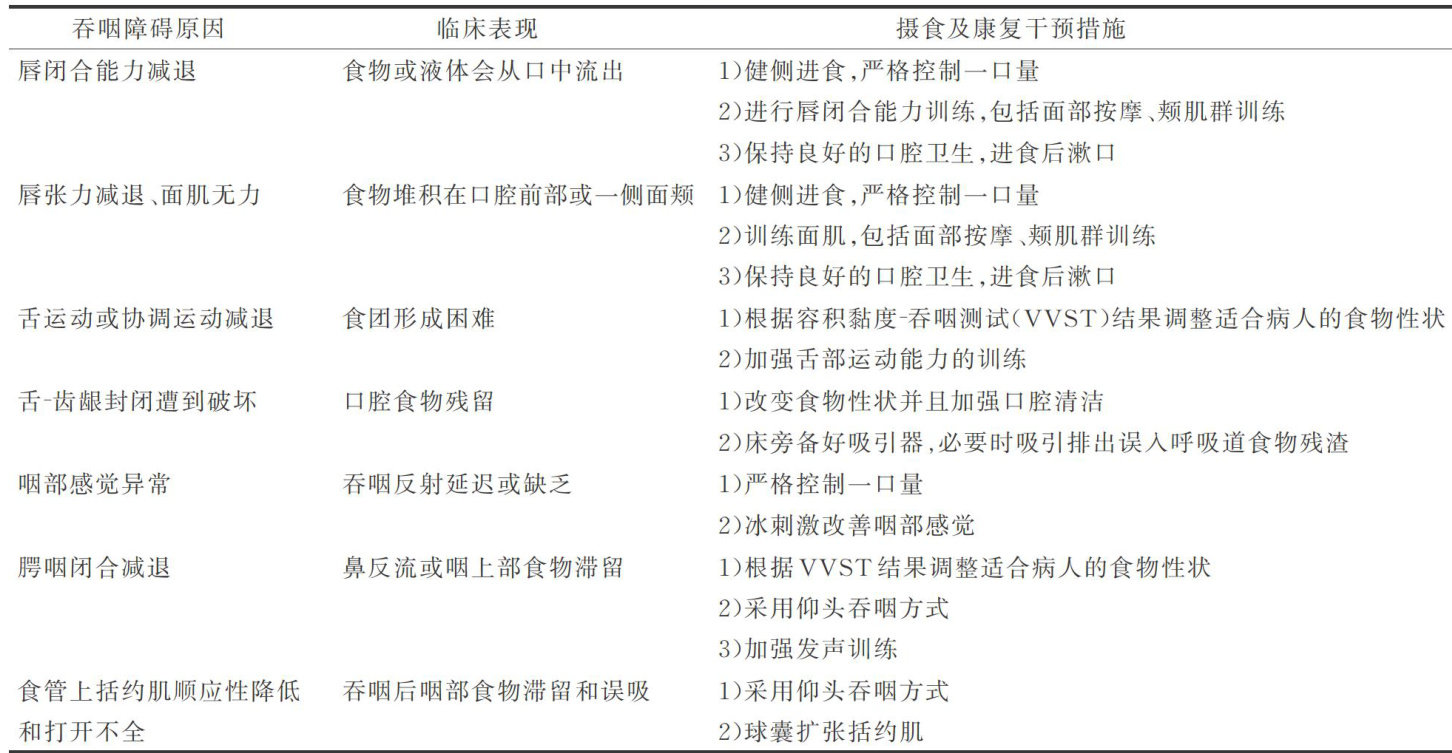

科研论著 | 脑卒中吞咽障碍病人精准摄食方案的构建及应用

科研论著 | 脑卒中吞咽障碍病人精准摄食方案的构建及应用